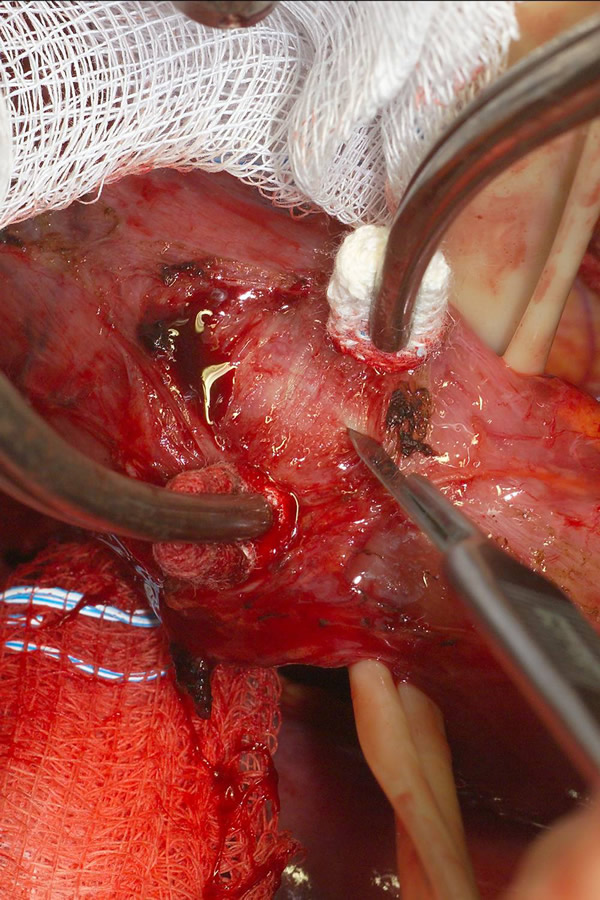

The surgical approach is a left posterolateral thoracotomy, entering the chest over the bed of the unresected 7th or 8th rib. On entering the thoracic cavity, the pulmonary ligament is divided and the lung is packed out of the way superiorly. The epiphrenic diverticulum is often found at the level of the inferior pulmonary vein. The pleura over the esophagus is divided allowing the esophagus to be gently mobilized. Penrose drains are used to encircle the esophagus superior and inferior to the diverticulum to facilitate the dissection (Figure 3). The diverticulum often arises to the right side necessitating rotation of the esophagus to clearly visualize the neck of the diverticulum. The diverticulum and its base are carefully dissected from the adjacent esophagus (Figure 4). Both vagus nerves are clearly identified and preserved during this maneuver. Once the diverticulum base is defined, a 40 Fr bougie is introduced across the gastroesophageal junction. This is performed under direct vision with the surgeon closely monitoring the safe passage of the bougie.